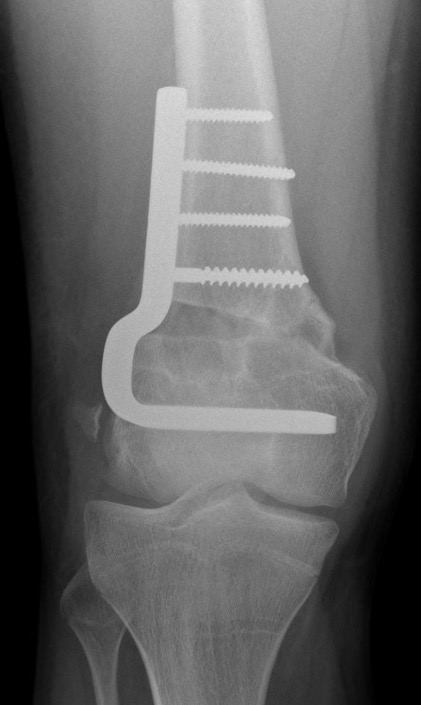

Distal Femur Salter Harris 2Distal Femur Salter Harris 2

Technique

AO foundation screw fixation Salter Harris Type II

- physeal sparing metaphyseal screws

Distal Femur SH2 ORIFDistal Femur SH2 ORIFDistal Femur SH2 Lateral